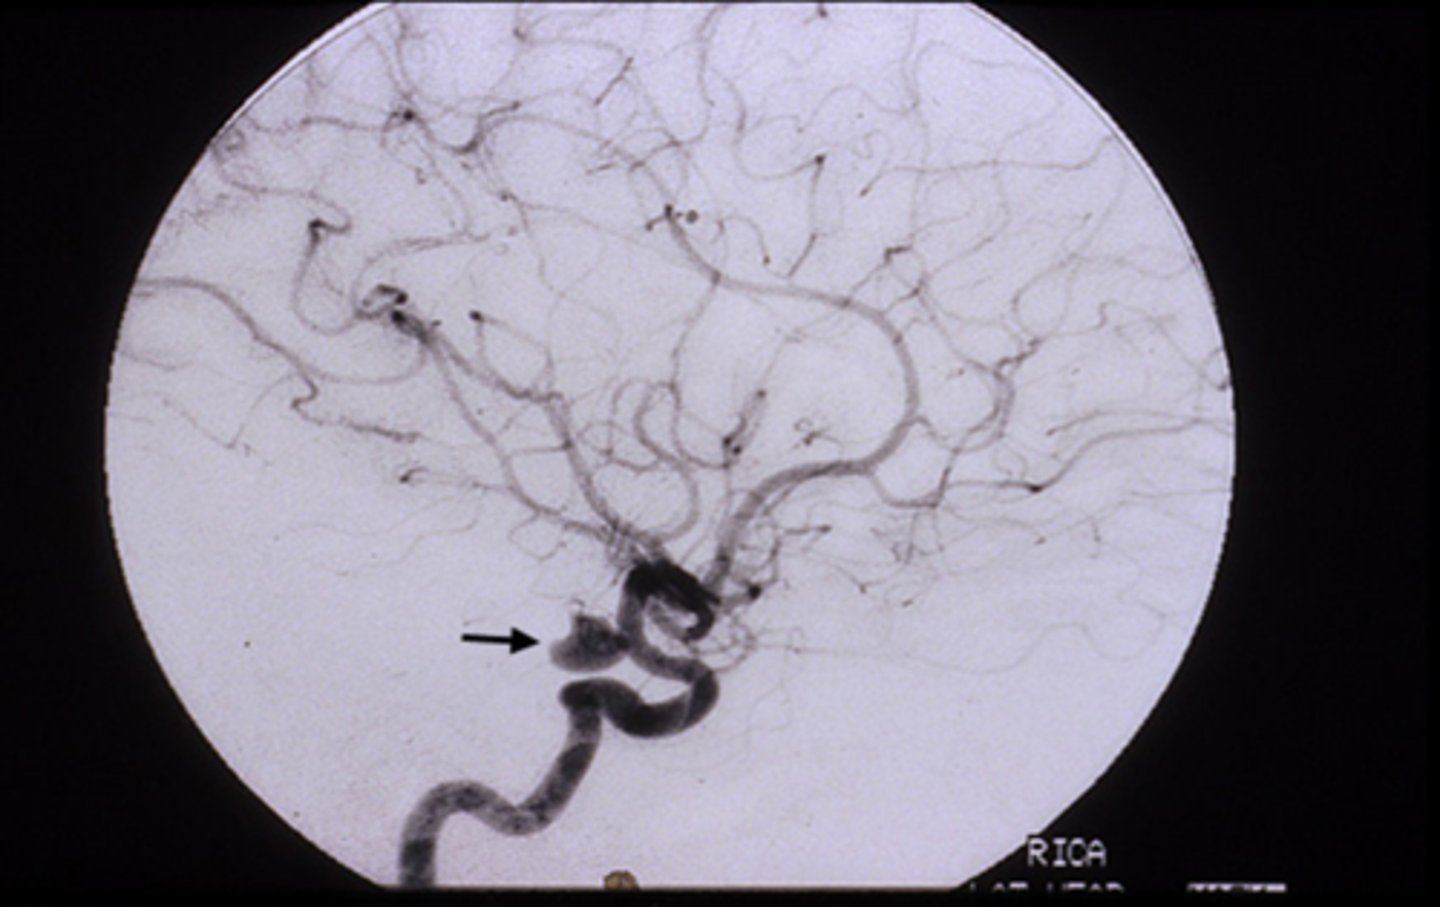

fixed, dilated pupil (esp if painful like HA) = anuerysm at the junction of the ICA and posterior communicating artery

pupil-sparing (may or may not be painful like eye pain) = diabetes or ischemic vascular etiology

NOTE: can change from pupil-sparing to pupil-involved if it is an aneurysm

Explain the anatomy of the pupillomotor vs EOM fibers in the CN III.

pupillomotor fibers travel around the circumference of CN III

EOM fibers travel within the core of CN III

Why are most pupil-spared CN III palsies the result of DM or vascular etiologies?

vasa nervorum occlusion = infarcation of these small BV = focal areas of demyelination in the nerve core, while the outer pupillomotor fibers are spared

Explain how the Uncal region can affect CN III in Uncal syndrome.

CN III leaves brainstem = pupillomotor fibers move dorsomedially = uncus herniates = compresses CN III dorsomedially against petroclinoid ligament and dorsum sellae = pupil is blown